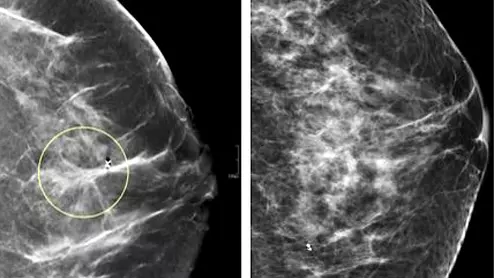

Comparison of a 2D digital mammogram and breast tomosynthesis 3D mammography from UCSF.

Although DBT exams are proven to identify more difficult to detect cancers, especially among women with dense breasts, they also include significantly more images than standard 2D mammograms.